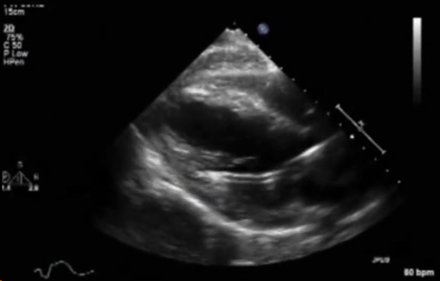

A 16-year-old female with fulminant viral myocarditis on peripheral veno-arterial (VA) ECMO support develops pulmonary hemorrhage. An Impella CP® device was inserted for left ventricular unloading while still on ECMO. A transthoracic echocardiogram was performed to confirm the position of the Impella due to concern for poor unloading. Based on the echocardiographic image below, what is the BEST next step in management?

On imaging, the Impella catheter appears as a bright linear echogenic structure crossing the aortic valve. The inlet is typically visualized just apical to the mitral valve plane and often displays a “teardrop sign”—an echolucent space representing blood being drawn into the pump.² The outlet should be in the proximal ascending aorta, not retracting into the valve or extending excessively. The pigtail tip (for Impella 2.5 and CP), visible as a curled loop extending toward the apex, helps reduce myocardial trauma and aids device orientation. Color doppler may reveal continuous flow from the LV to the aorta through the device when the device is properly placed and functioning. Figure 1 shows an example of incorrect positioning, as the inlet is located in the LV myocardium, while Figure 2 demonstrates the correct positioning of the Impella. The inlet positioning should be approximately 3.5–4 cm from the aortic annulus for Impella CP and 5.0, and 5 cm from the aortic annulus for the Imeplla 5.5.²

Figure 1: Improper Impella Placement. This figure shows the impella is advanced too far into the LV cavity, which can cause obstruction to blood flow in the inlet of the impella device.